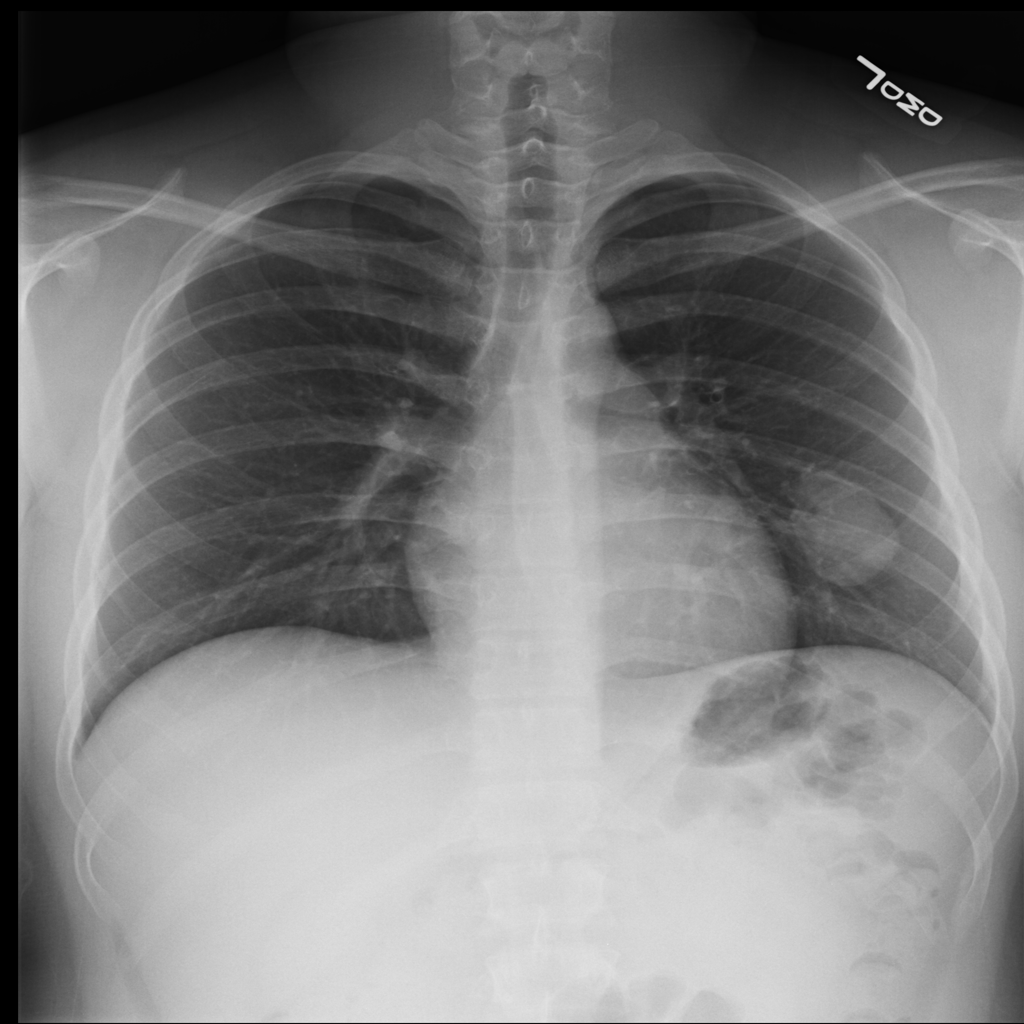

PAT-50E5 · IMG-008Mass

PAT-50E5 · IMG-008

PA